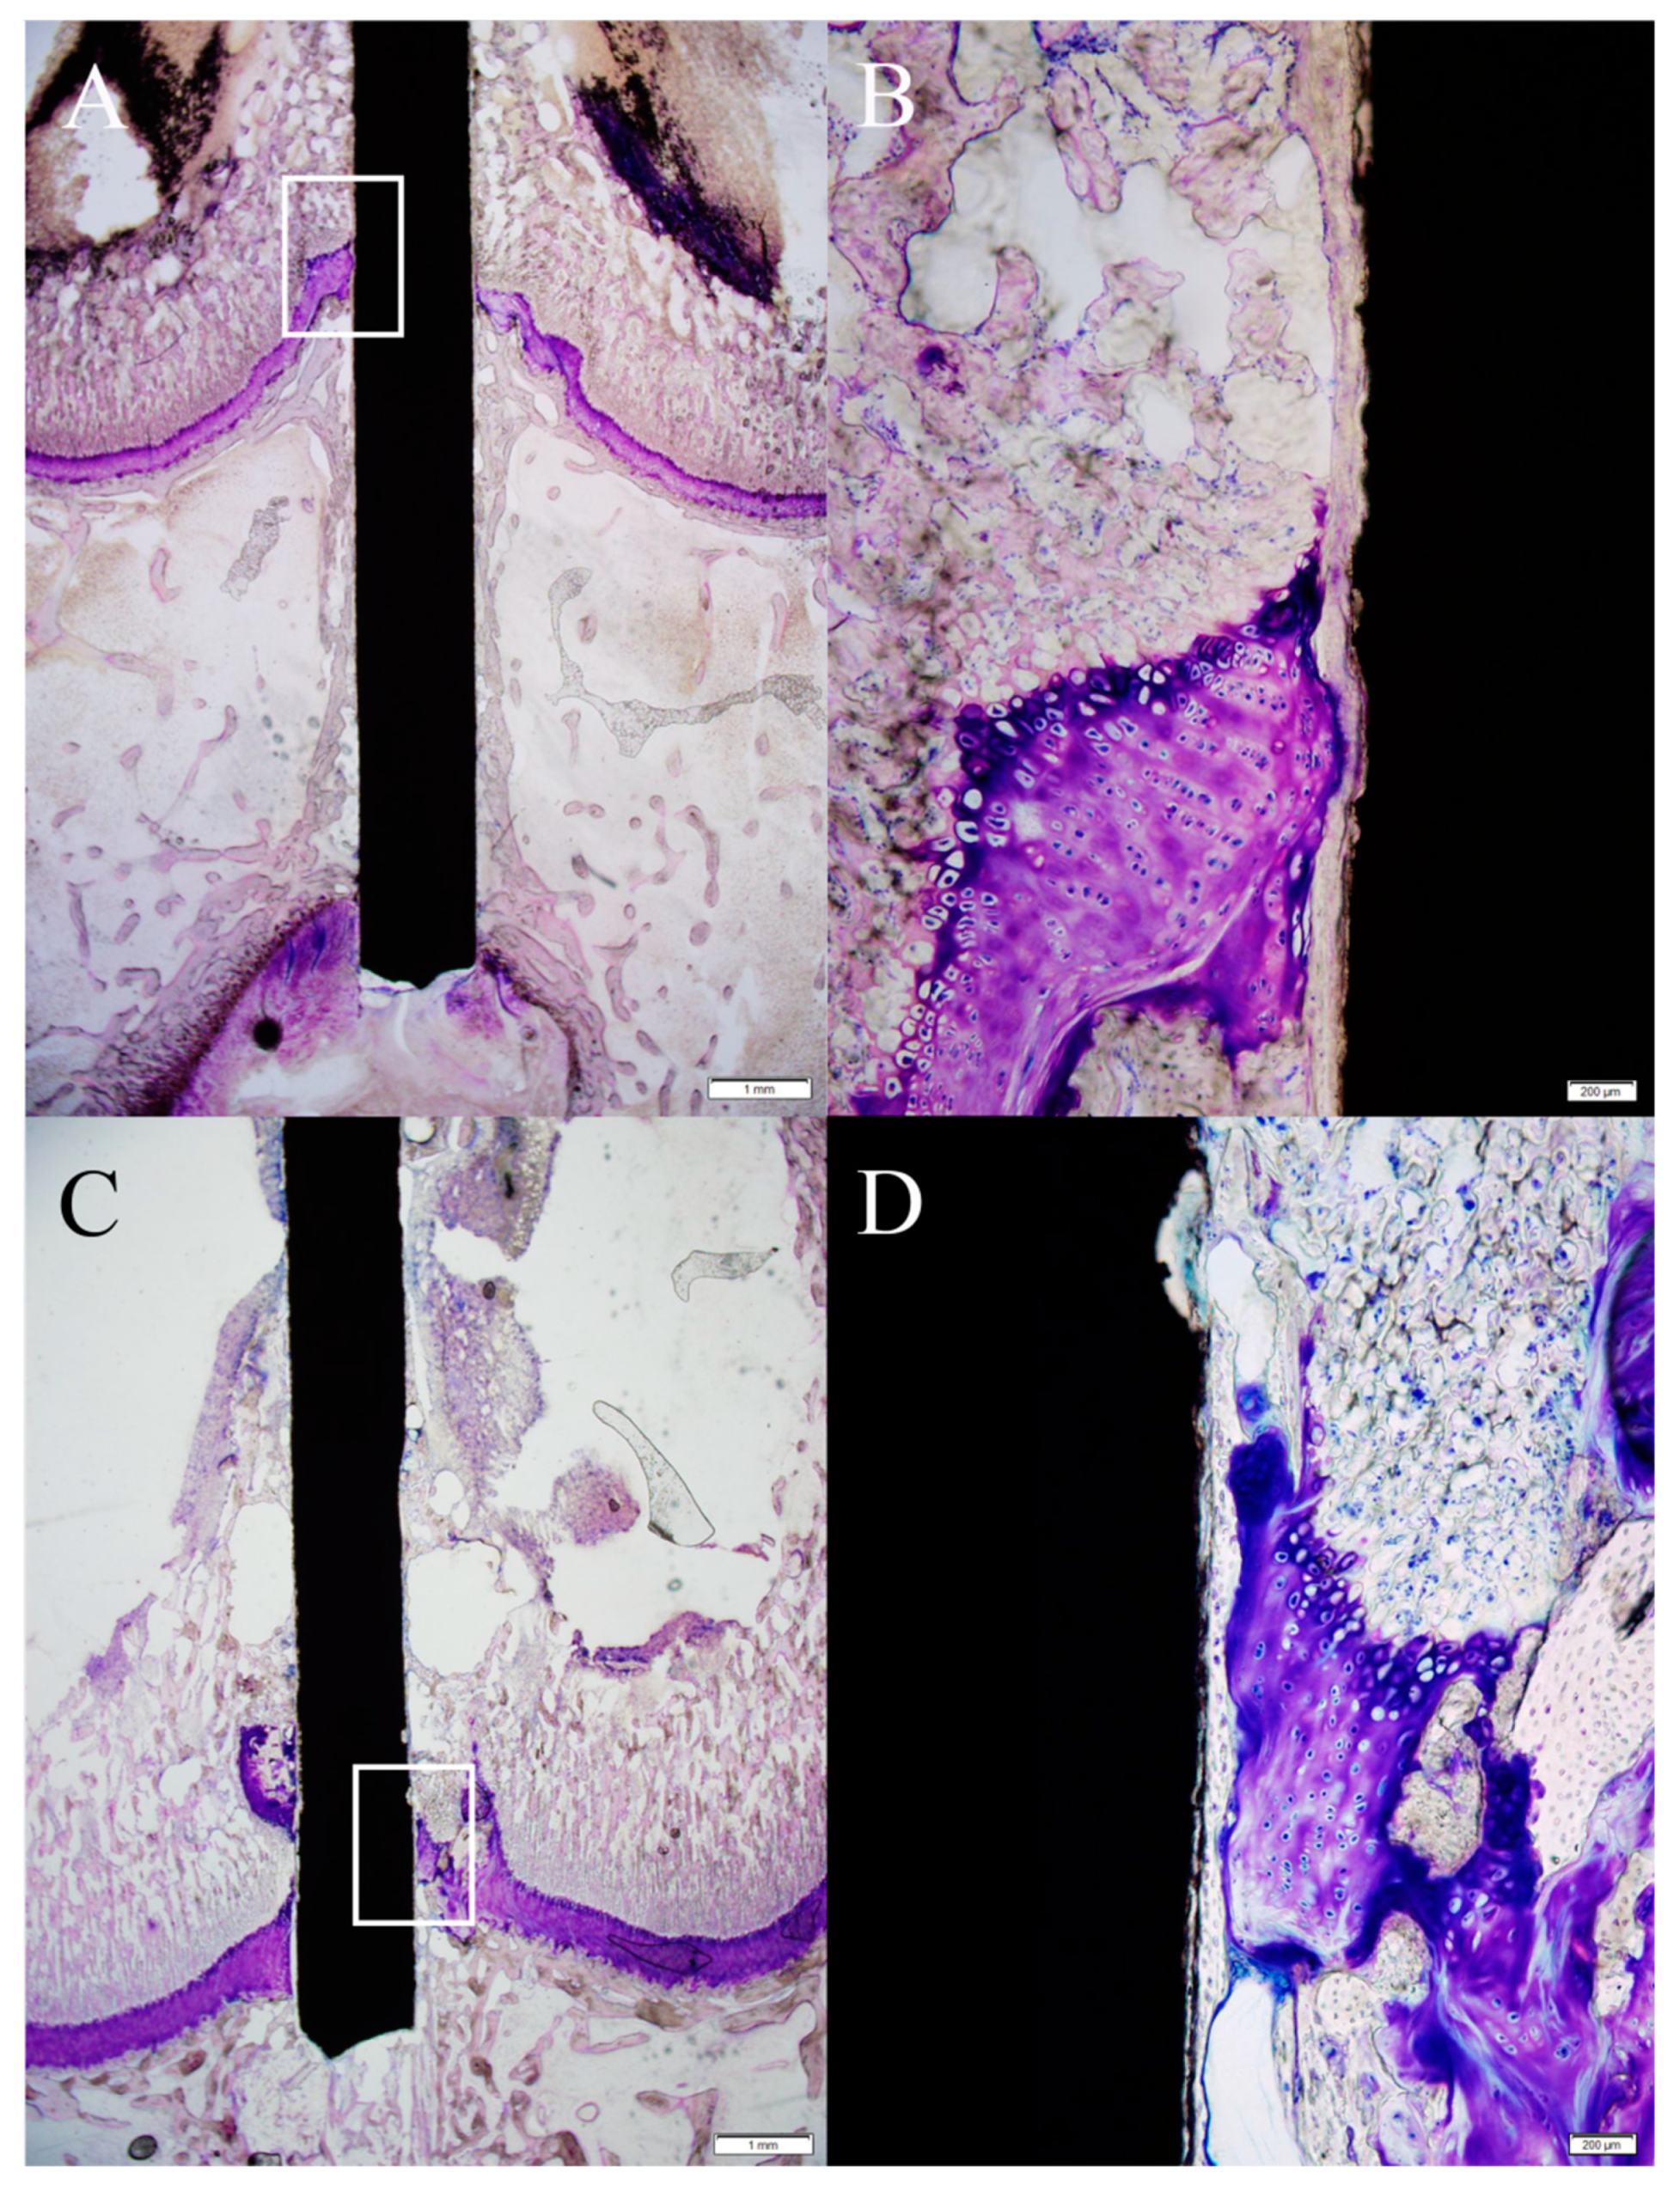

2.3. Influence of the Mg-Ca-Zn Alloy Pin on the Growth Plate